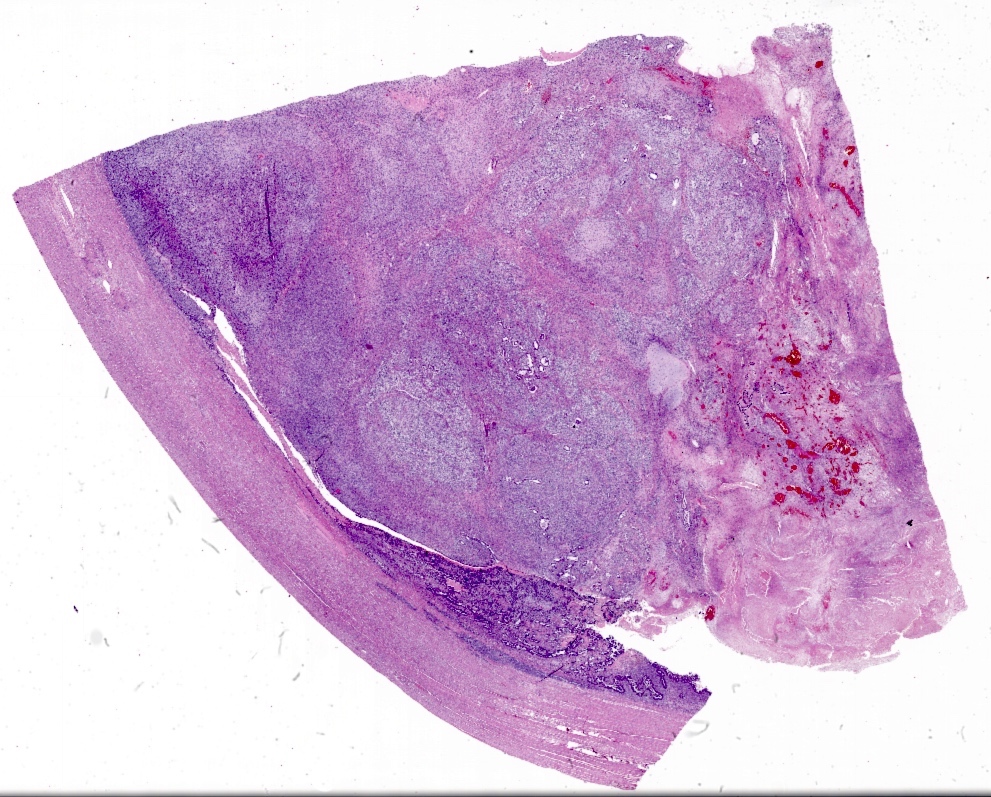

Microscopic (histologic) description

- Biphasic tumor with carcinomatous and sarcomatous elements, both high grade (Int J Gynecol Pathol 1990;9:1)

- Carcinomatous and sarcomatous components are juxtaposed

- Carcinomatous elements:

- Often high grade endometrioid or serous carcinoma, frequently admixed

- More uncommonly clear cell carcinoma

- 50 - 75% of cases have serous or mixed serous and high grade endometrioid carcinoma (Am J Surg Pathol 2007;31:1653)

- Hybrid morphology between endometrioid and serous carcinoma is frequent, as is undifferentiated carcinoma (Mod Pathol 2010;23:781)

- Other components that can be rarely found are squamous, mucinous and neuroendocrine

- Sarcomatous elements:

- Often spindle and pleomorphic

- 50% contain heterologous elements (most commonly rhabdomyosarcoma and chondrosarcoma) (Am J Surg Pathol 2007;31:1653)

- Osteosarcomatous, liposarcomatous and angiosarcomatous differentiation are less common (Semin Diagn Pathol 1988;5:199, Arch Pathol Lab Med 1991;115:583, Int J Gynecol Pathol 2017;36:140)

- Carcinomatous elements:

- Angiolymphatic invasion common, more commonly of the carcinomatous component

Microscopic (histologic) images